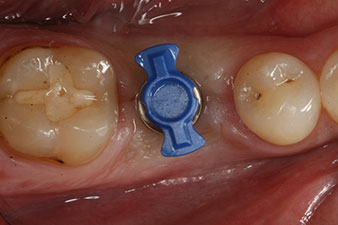

Имплантът е поставен както е планирано след цялостно отстраняване на гранулационната тъкан (blueSky, bredent).

Въртящият момент, използван за машинно-задвижвано поставяне, е 43 Ncm. Освен това, след завинтване на измервателния щифт (SmartPeg), специално пригоден за импланта, стойността на ISQ се измерва със сондата на W&H Osstell ISQ модула.

Този модул е допълнителна екстра към Implantmed на W&H и е закачен към имплантологичния мотор (виж фиг. 11). Липсата на ISQ стойност непосредствено след поставянето е 64 оровестибуларно и 68 мезиодистално (максимална стойност = 100).

Тези стойности могат да показват отворено лечение или дори имедиатно възстановяване. Поради недостатъчния обем на кресталната кост при импланта, областта е подсилена с костните частици, събрани по време на препарацията на имплантното ложе и зашити, за да се изолира слюнката.